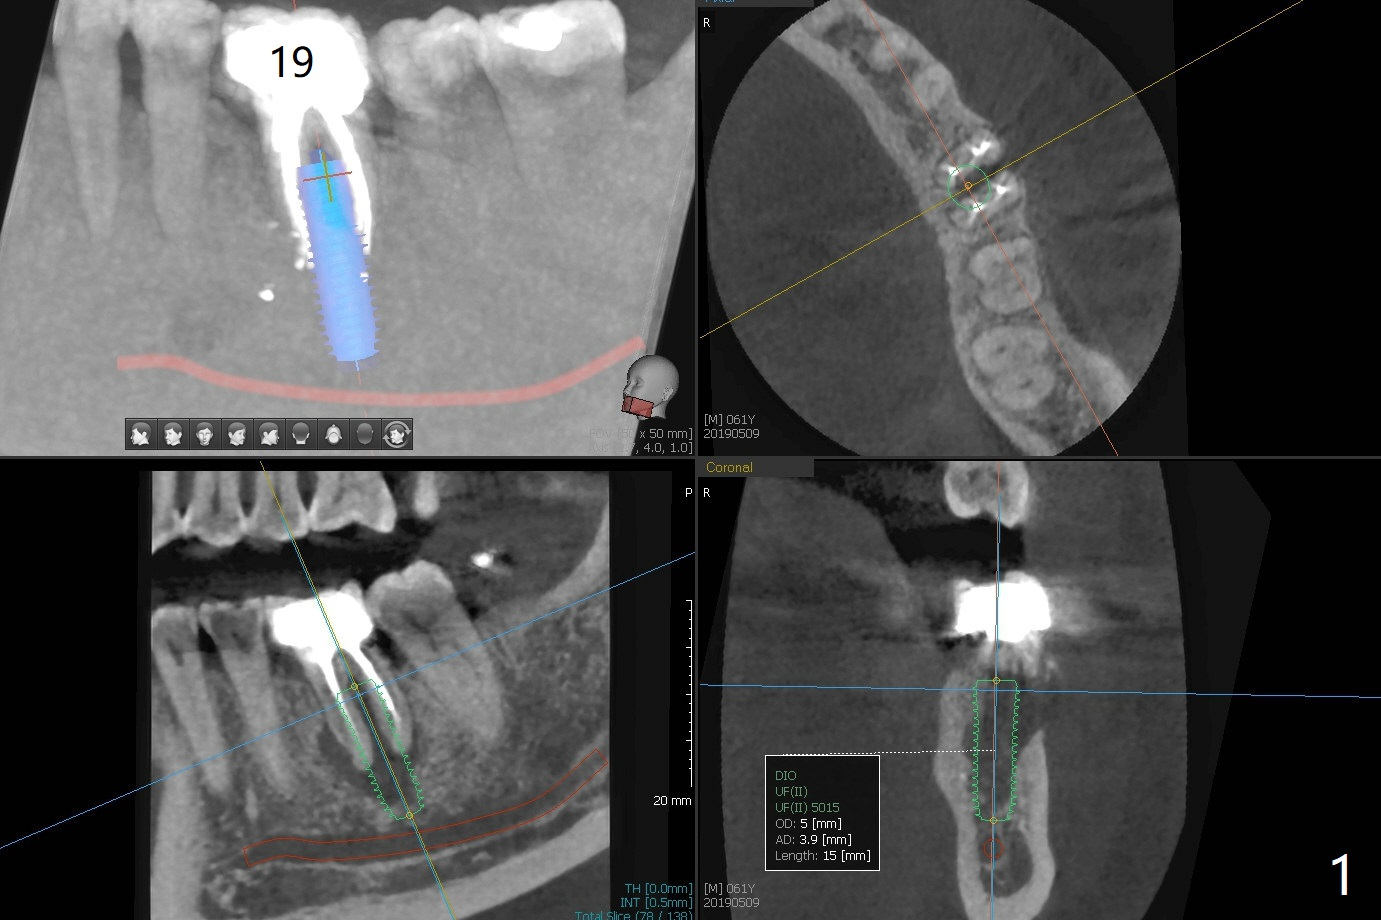

The tooth #19 of a 61-year-old man develops pain 9 years post complicated RCT (Fig.1). Periradicular radiolucency is more around the mesial root (Fig.2) than the distal one (Fig.3). Section the crown to check whether the distal margin is restorable. Remove the mesial root to determine whether the distal one is salvageable or not. If not, place a 5x15 mm bone-level implant with guide. To reduce the chance of screw loosening, consider placing a tissue-level implant (Fig.4,5). Preserve the buccal crestal bone (Fig.6 *) during extraction and debridement, which keeps the socket open for bone graft and healing. Draw blood for PRF PRN for membrane and sticky bone.